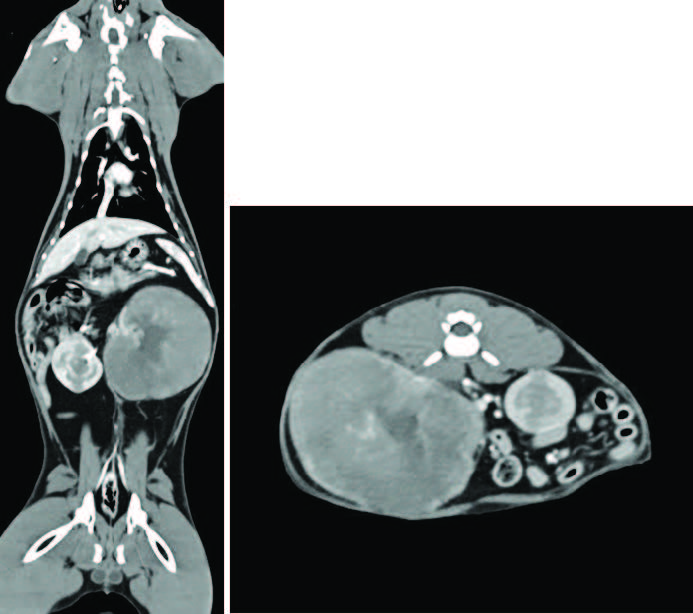

胸腹CT血管造影显示左肾显著增大,约80×65×90 mm,结构明显变形,皮髓质分界消失,呈巨大分叶状膨胀性改变(图1);肿物效应致小肠严重右移,脾脏向前左侧卷曲移位。右肾轻度增大,长约50 mm,皮髓质内见多个膨胀性圆形病灶。其余CT表现无异常。

图1. 软组织窗CT扫描(左冠状面、右轴面)。左肾显著增大,约80×65×90 mm,结构明显变形,皮髓质分界消失,呈巨大分叶状膨胀性改变。皮质及髓质对比增强减弱,而组织不规则外周缘对比增强增强。其中心仍保留类似肾盂的区域,可见左肾动、静脉进入,但无对比剂积聚。左肾产生占位效应,致肠管严重右移;脾脏向前左侧卷曲移位。右肾轻度增大,长约5 cm,皮髓质内见数个膨胀性圆形病灶,轻度扭曲肾外形;平扫时与髓质密度相近(约40 HU),但增强后对比增强明显降低。